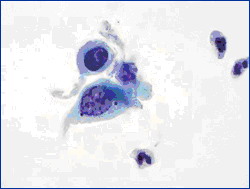

举例来说,慢性宫颈炎(宫颈糜烂)与宫颈癌在妇科阴道镜检查时观察到的表现可以相似。行宫颈刮片的细胞检查时看到的也可以相似(图1、2)。最后采取组织行病理切片检查,也是有相似之处,不是容易做出100%鉴别的(图3、4)。这样看来,如果仅一次检查(或一家医院检查),就肯定是癌,而行手术切除,是不慎重的,错误率是高的。最好是如果要手术切除,应到第二家医院或第二个医生核实后进行下一步治疗。

图2 宫颈癌看到的细胞